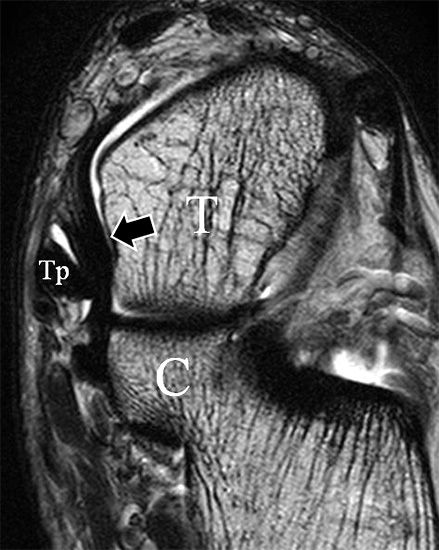

Man unterscheidet bei dem Ligamentum deltoideum eine tiefe Schicht (Pars tibiotalare posterior, Pars tibiotalare anterius) und eine oberflächliche Schicht (Pars tibionaviculare, Pars tibiocalcaneare, Pars tibiotalare posterius superficialis und Tibiospring-Ligament) 10. Hochauflösende Techniken lassen eine differenzierte Beurteilung aller Bandanteile zu. Sowohl rein ligamentäre als auch osteo-ligamentäre Ausrisse sind normalerweise gut zu erkennen. Die Pars tibiotalaris posterior ist multifaszikulär aufgebaut und sowohl axial als auch coronar (Abb. 19 a) gut bildgebend abzugrenzen. Die deutlich kleinere, nur inkonstant angelegte Pars tibiotalare anterior inseriert an einem kleinen Talustuberkel (Abb. 19 b). Ossäre Bandausrisse kommen hier gehäuft vor. Proximal verlaufen die Pars tibiocalcaneare und die Pars tibionaviculare gemeinsam (Abb. 19 c) nach kaudal und trennen sich dann in zum Calcaneus und zum Os naviculare ziehende Bündel auf. Ein besonderer Typ ligamentärer Verbindungen stellt das Tibiospring-Ligament dar. Es verbindet nicht wie für Ligamente typisch zwei Knochen miteinander, sondern es hat seinen ossären Ursprung an der Tibia und inseriert am Pfannenband (Ligamentum calcaneonaviculare plantare, im englischen Schrifttum Spring-Ligament genannt), also nicht ossär. Das Innenband ist mit 60% der Verletzungen am häufigsten betroffen. Isolierte Innenbandverletzungen sind jedoch selten. Sie treten gehäuft assoziiert mit Syndesmosenläsionen, Fibulafrakturen, Verletzungen des Muskulus tibialis posterior und des Pfannenbandes auf (H.-K. Beyer 2003). Entsprechend sollte auf diese Kollateralverletzungen bei der Beurteilung geachtet werden. Eine weitere Folge von Verletzungen des Ligamentum deltoideum ist die chronische Sprunggelenksinstabilität. Arthroskopisch weisen hier bis zu 40% der Patienten einen elongierten Verlauf des Ligamentum deltoideum auf. In diesem Patientenkollektiv besteht auch eine erhöhte chondrale Komorbidität mit arthroskopisch erkennbaren Knorpelschäden (98%) im Gegensatz zu der Patientengruppe (66% Knorpelschäden) mit reiner Außenbandinstabilität 11. Dies belegt die klinische Bedeutung von Innenbandverletzungen.